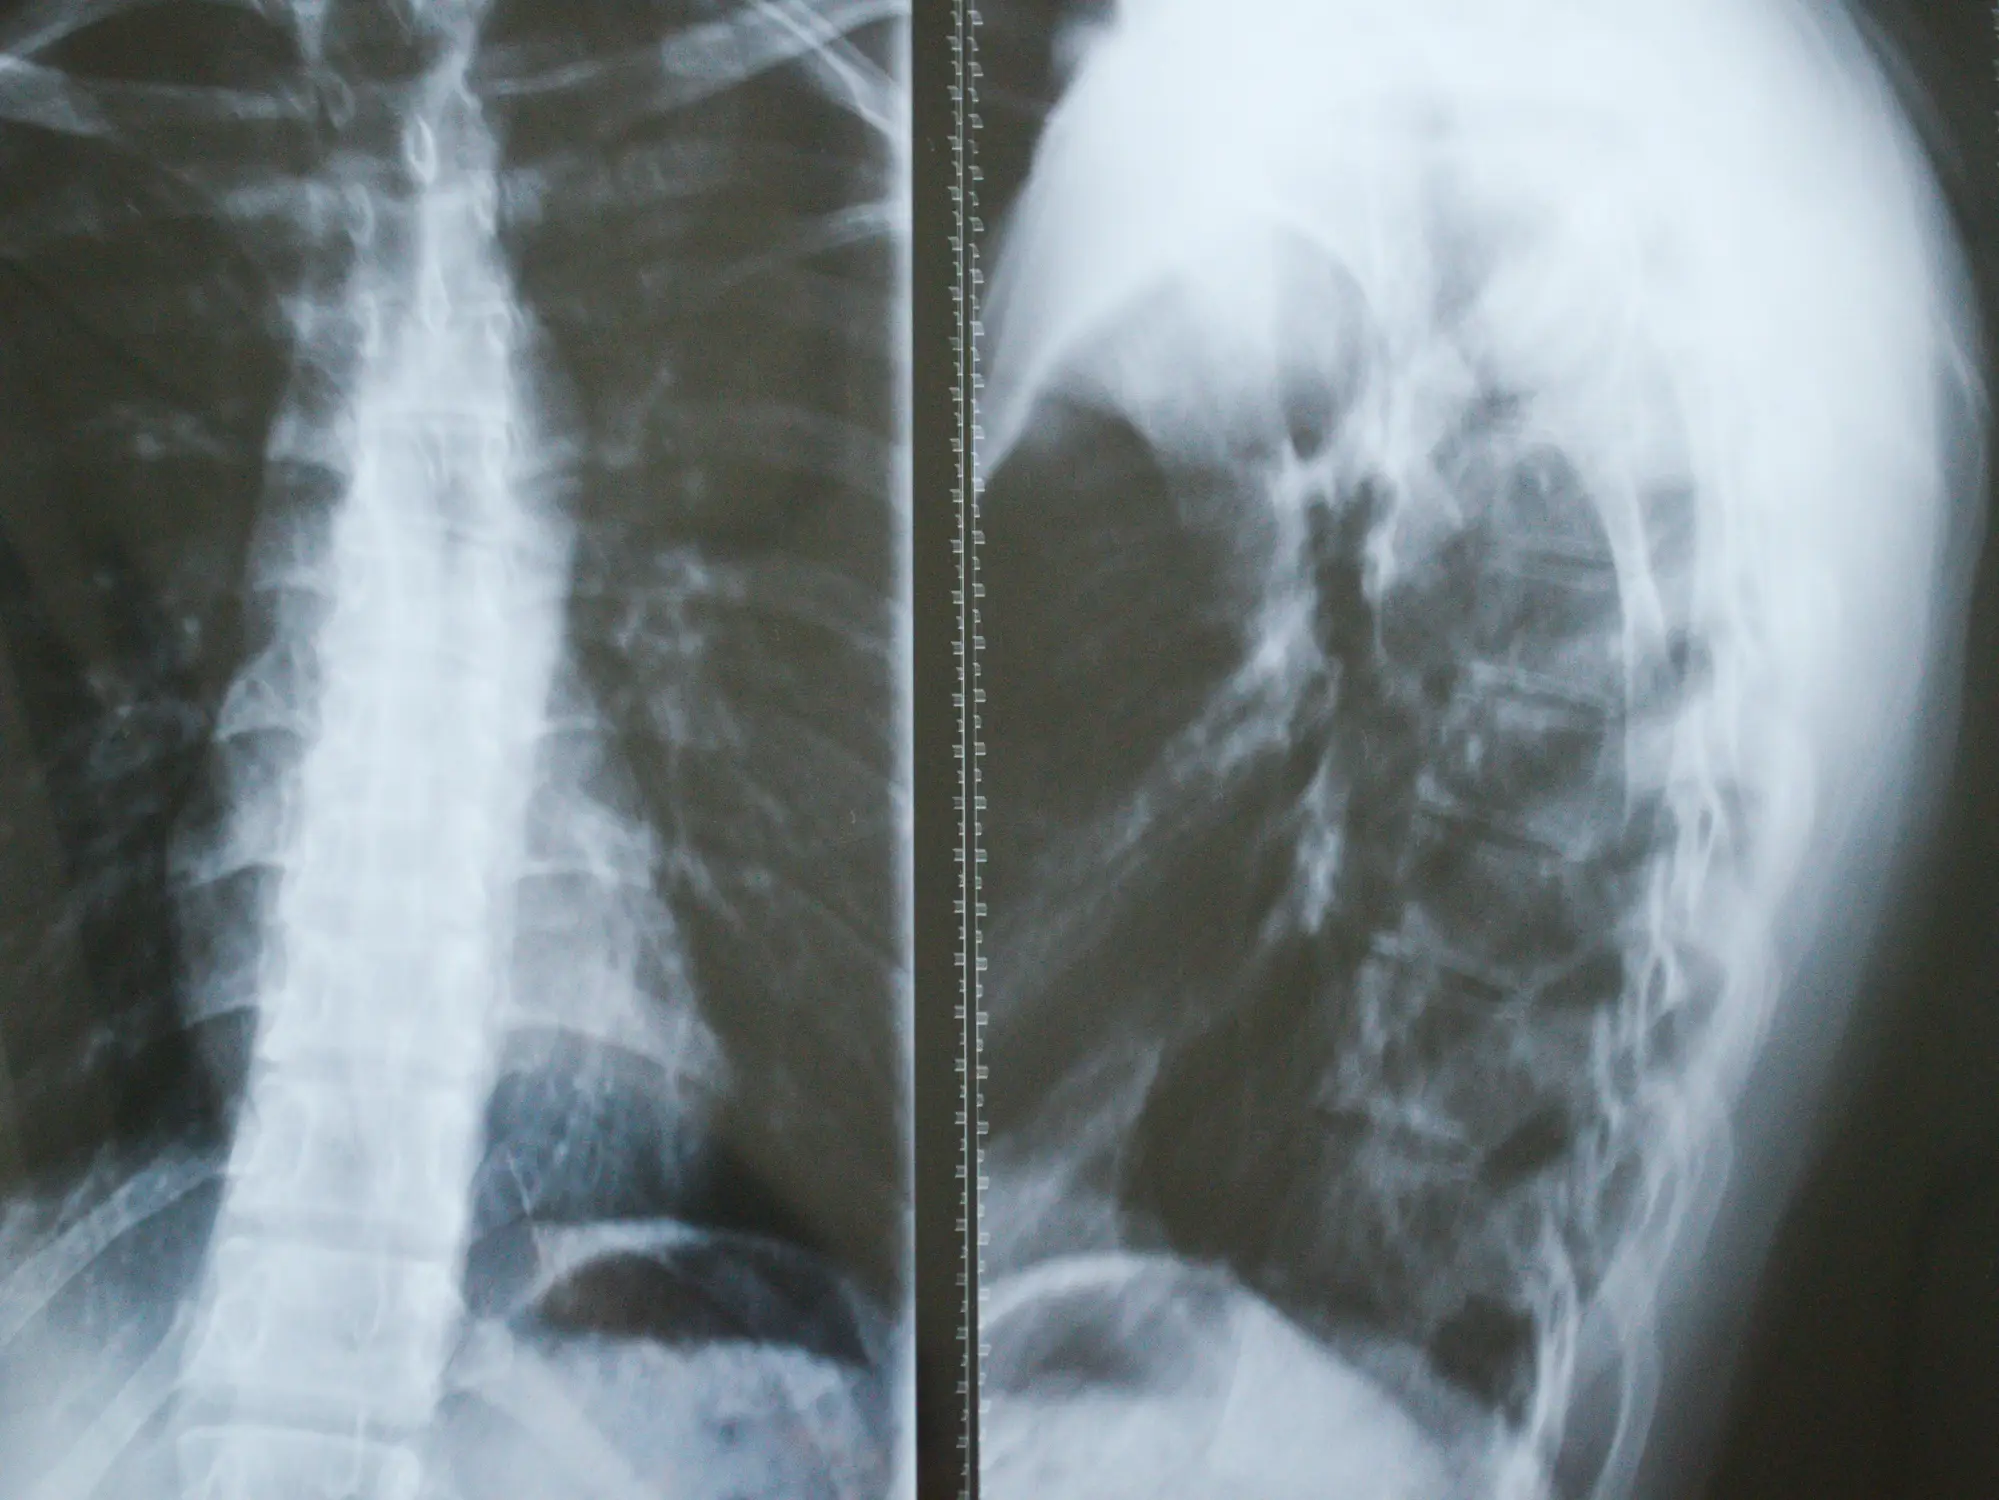

Doctors rely on imaging scans to track bone loss and typically confirm the condition through a bone biopsy, which shows non-cancerous vascular tissue replacing bone.